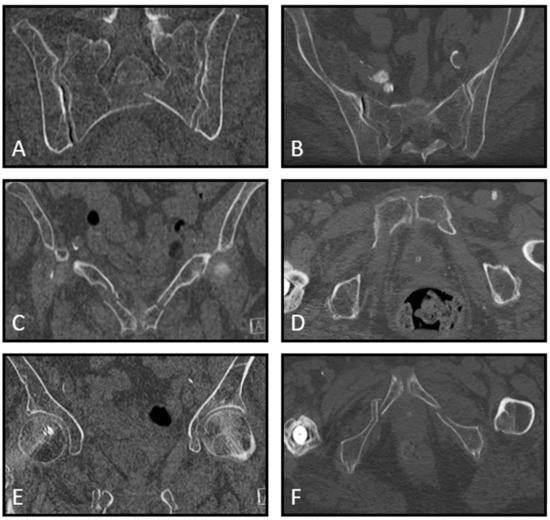

| 12. Mrs. A. is a 75-year-old, independently living ASA 2 patient. She tripped and fell at home. Plain radiographic imaging showed a superior/inferior ramus fracture on the left side. Would you, based on this information, perform a CT scan in the hospital you work at? | A. No, a CT scan has no treatment consequences B. Yes, always C. Yes, if the patient has pain on palpation of the sacrum D. Yes, if the patient is very painful during mobilization E. Otherwise, namely: |

| 13. Mrs. B. is a 77-year-old ASA 4 patient living in sheltered housing. She tripped and fell at home. Plain radiographic imaging showed a superior/inferior ramus fracture on the left side. Would you, based on this information, perform a CT scan in the hospital you work in? | A. No, a CT scan has no treatment consequences B. Yes, always C. Yes, if the patient has pain on palpation of the sacrum D. Yes, if the patient is very painful during mobilization E. Otherwise, namely: |

| 14. Mrs. C. is a 75-year-old, independently living ASA 2 patient. She fell on the street, and plain radiographic imaging showed a superior/inferior ramus fracture on the right side. She is discharged from the ER with oral painkillers. The patient comes back to your outpatient clinic after 14 days. She mobilizes with difficulty, sits in a wheelchair, walks with a four-wheel walker indoors, and uses Paracetamol and Diclofenac. A CT scan shows an LC1/FFP3c fracture. Do you think, based on this information, the patient is eligible for surgical fixation? | A. No, I do not think this is indicated and would have little impact on this patient’s outcome B. No, I think operative pelvic fixation would be too invasive for this patient C. Yes, if the patient has evident pelvic pain during a physical exam D. Yes, only if the pain did not decrease at 6 weeks follow-up E. Otherwise, namely: |

| 15. Mrs. D. is a 69-year-old, independently living ASA 3 patient with COPD Gold 3. She fell on the street, and plain radiographic imaging showed a superior/inferior ramus fracture on the right side. She is discharged from the ER with oral painkillers. The patient comes back to your outpatient clinic after 14 days. She mobilizes with difficulty, sits in a wheelchair, walks with a four-wheel walker indoors, and uses Paracetamol and Diclofenac. A CT scan shows an LC1/FFP3c fracture. Do you think, based on this information, the patient is eligible for surgical fixation? | A. No, I do not think this is indicated and would have little impact on this patient’s outcome B. No, I think operative pelvic fixation would be too invasive for this patient C. Yes, if the patient has evident pelvic pain during a physical exam D. Yes, only if the pain did not decrease at 6 weeks follow-up E. Otherwise, namely: |

| 16. Mrs. E is an 81-year-old ASA 3 patient. She fell on the street, and plain radiographic imaging showed a superior/inferior ramus fracture on the right side. She is admitted to the nursing ward and has difficulty turning in bed. Transfer from bed to toilet chair is possible. She uses Paracetamol, Diclofenac and Oxynorm. A CT scan shows an LC1/FFP3c fracture. Do you think, based on this information, the patient is eligible for surgical fixation? | A. No, I do not think this is indicated and would have little impact on this patient’s outcome B. No, I think operative pelvic fixation would be too invasive for this patient C. Yes, if the patient has evident pelvic pain during a physical exam D. Yes, only if the pain did not decrease at 6 weeks follow-up E. Otherwise, namely: |